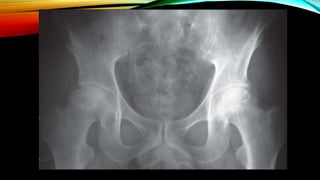

FILM: BOTH HIP AP

HOW TO DIAGNOSE AVN OF

FEMORAL HEAD?

• Radiograph (X-ray or MRI)

-Ficet and Arlet classification system